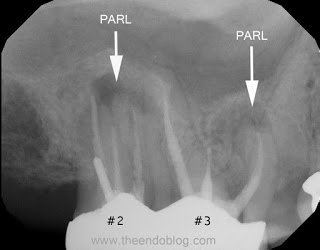

Endodontic diagnosis, including CBCT, determines that tooth #2 has a prior root canal with a root fracture and extraction is recommended. Tooth #3 has a prior RCT with apical abscess – caused by a missed MB#2 canal during the initial root canal treatment. Retreatment of the root canal #3 is recommended.